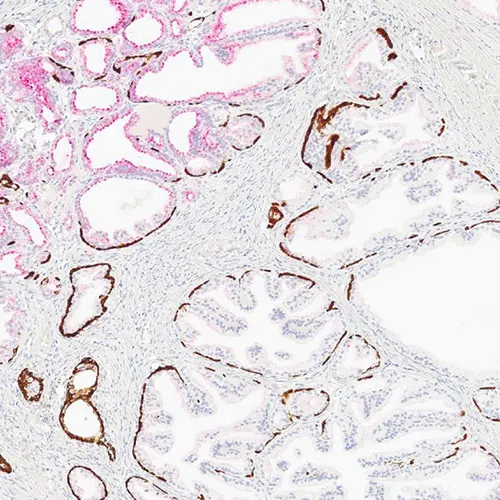

• Stable red and brown chromogens in one detection kit

• Crisp and clear red and brown staining, allowing for excellent ease of interpretation